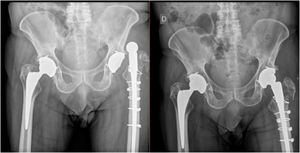

La tasa de revisión para todas las causas fue del 28,9%. El 26% de los pacientes tuvieron al menos un episodio de inestabilidad, siendo la tasa de infección del 5,3%. En el subgrupo de pacientes con un episodio de luxación (n=10), 6 pacientes (60%) tuvieron un tamaño de cabeza femoral de 32mm o inferior, siendo de 36mm en 2 pacientes (20%), y careciéndose de información acerca de dicho tamaño en 2 pacientes (20%).

El 71% de los pacientes con fractura de GT tuvieron al menos un episodio de inestabilidad (p=0,008) (tabla 4 y fig. 3). El hecho de si la fractura de GT se fijó o no, así como el tipo de fijación, no revelaron diferencias en cuanto a la tasa de inestabilidad (p>0,05).

La presencia de fractura del trocánter mayor fue una variable clave de la inestabilidad, teniendo el 71,4% de los pacientes con dicha fractura al menos un episodio de la misma (p=0,008). De manera interesante, la realización de osteosíntesis de GT y los diversos tipos de osteosíntesis no revelaron diferencias en cuanto al tipo de inestabilidad (p>0,05). A pesar de que la fractura de GT es un factor de inestabilidad bien establecido11,30, este hallazgo aporta una significación ominosa a esta lesión (fig. 4). La osteosíntesis de la fractura de GT es a menudo difícil, debido al desplazamiento de la fractura por la tracción de los músculos del glúteo30 y al pobre stock óseo, ya que a menudo dichas fracturas están asociadas a osteólisis11.